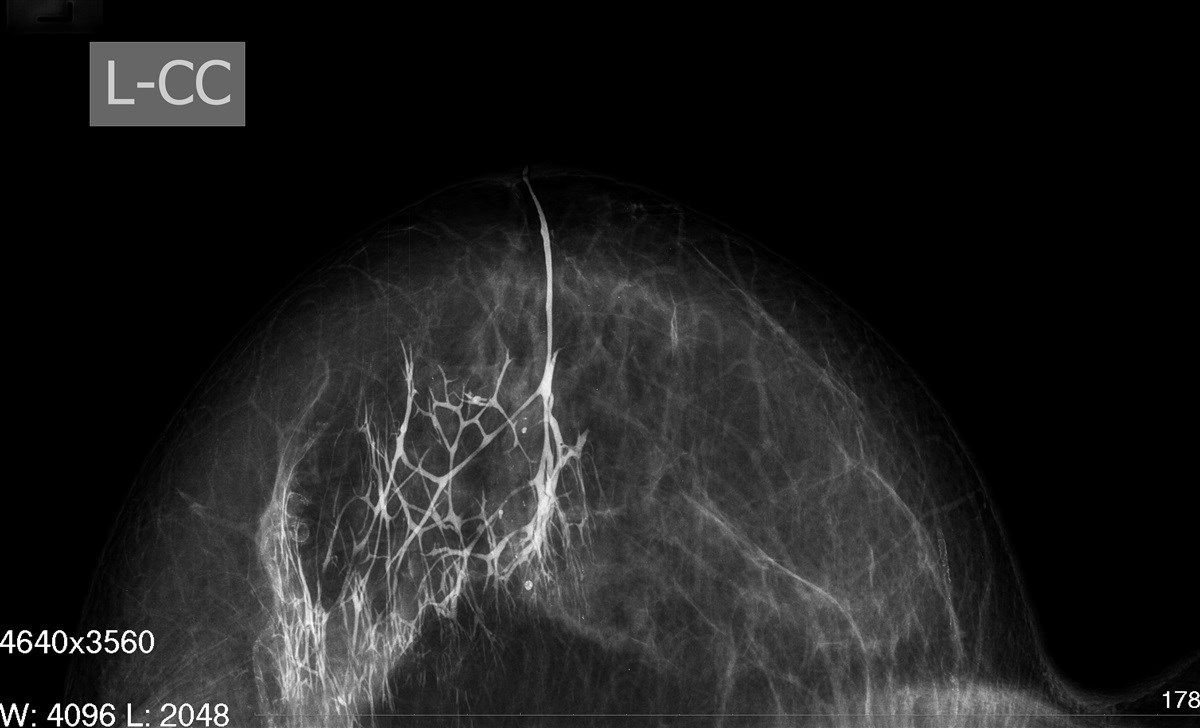

- Маммография — рентгеновский снимок молочной железы. Определяет присутствие опухолей, их размеры и размещение. Недостаток маммографии – она не помогает изучить внутреннее строение нароста. Обычно её используют при обследовании женщин постарше, когда упругость железы снижается.

- Дуктография молочных желез – рентгенография каналов с добавлением контрастного вещества. Помогает изучить образование в молочных железах изнутри, участки повреждения, расположение относительно других тканей, возможную онкогенность. Особенность процедуры заключается в вводе контраста в главный проток, открывающийся в соске. На фото выше показан результат дуктографии.

Маммография представляет собой рентген груди. Снимки показывают локализацию бородавок и их форму. Однако данная диагностика не позволяет изучить наросты изнутри, что затрудняет объективную оценку состояния молочных желез.

Дуктография представляет собой рентген с введением контрастного вещества в главный проток — через сосок. Этот метод позволяет выявить не только локализацию и форму бородавок в протоках, но и определить вероятную онкогенность. Дуктография невозможна при наличии атипических клеток.

- Маммографическое обследование. Проводится рентгенография органа для обнаружения пораженного участка, выяснения размеров, области расположения внутреннего образования;

- Дуктографическое исследование. В отличие от маммографии позволяет более точно установить тип, размеры, расположение микровыроста. При проведении обследования применяется контрастное вещество, заполняющее протоки органа. Проведение дуктографии необходимо, если назначена операция по удалению грудной железы.